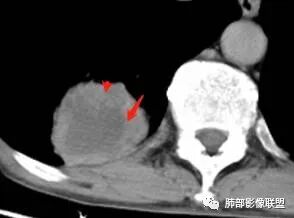

一、本例主要分析右肺下叶病灶:

主要征象:病灶分叶不明显、较光整,局部胸膜栽赃,支气管门口堵塞,有推移迹象;增强后坏死明显,内部囊变坏死边缘部分清楚、部分不清楚,病灶内可见血管,局部稍毛糙,实性部分强化较明显,总体考虑恶性病变。一部分征象指向鳞癌(支气管截断、坏死较多,病灶内血管破坏),但又有肉瘤的一些特点(病灶较大,缺乏分叶,坏死边界清晰),要考虑到肉瘤样癌。